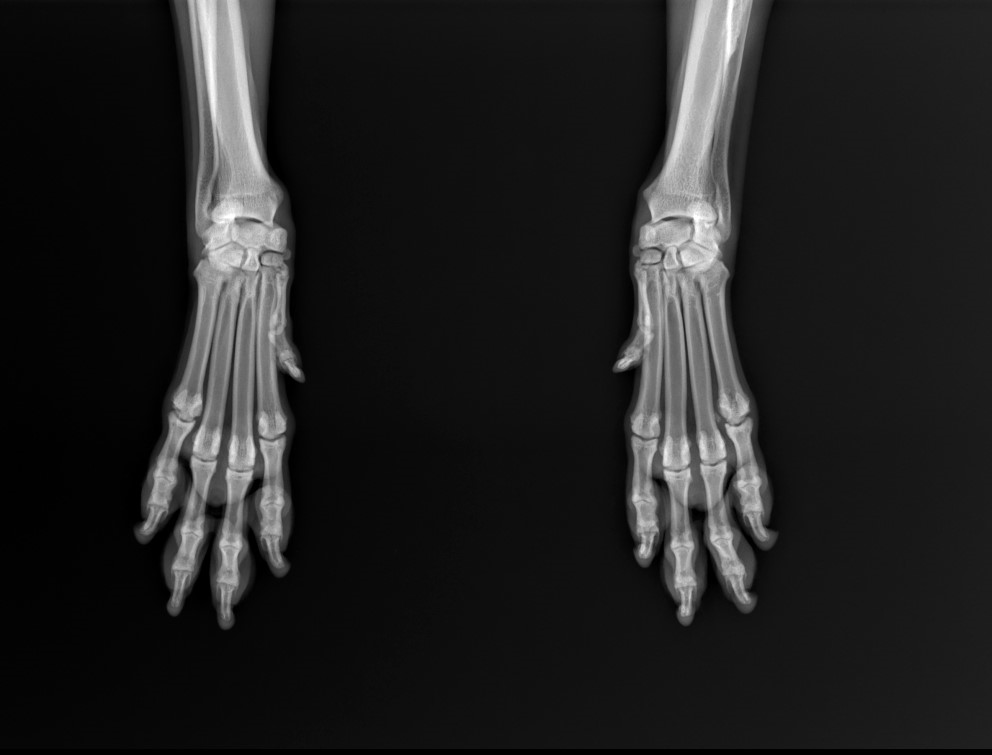

Radioulnar Synostosis

Female, 7.5 yo, 27 kg, mixed breed dog

presented with chronic 2 grade left forelimb lameness

Orthopedic examination did not detect abnormalities, x-ray with awake patient was performed on forelimb (medio-lateral view of elbows and dorso-palmar view of carpus).

Diagnosis of severe left Elbow Dysplasia with radio-ulnar synostosis presumably

as a result of an old fracture.